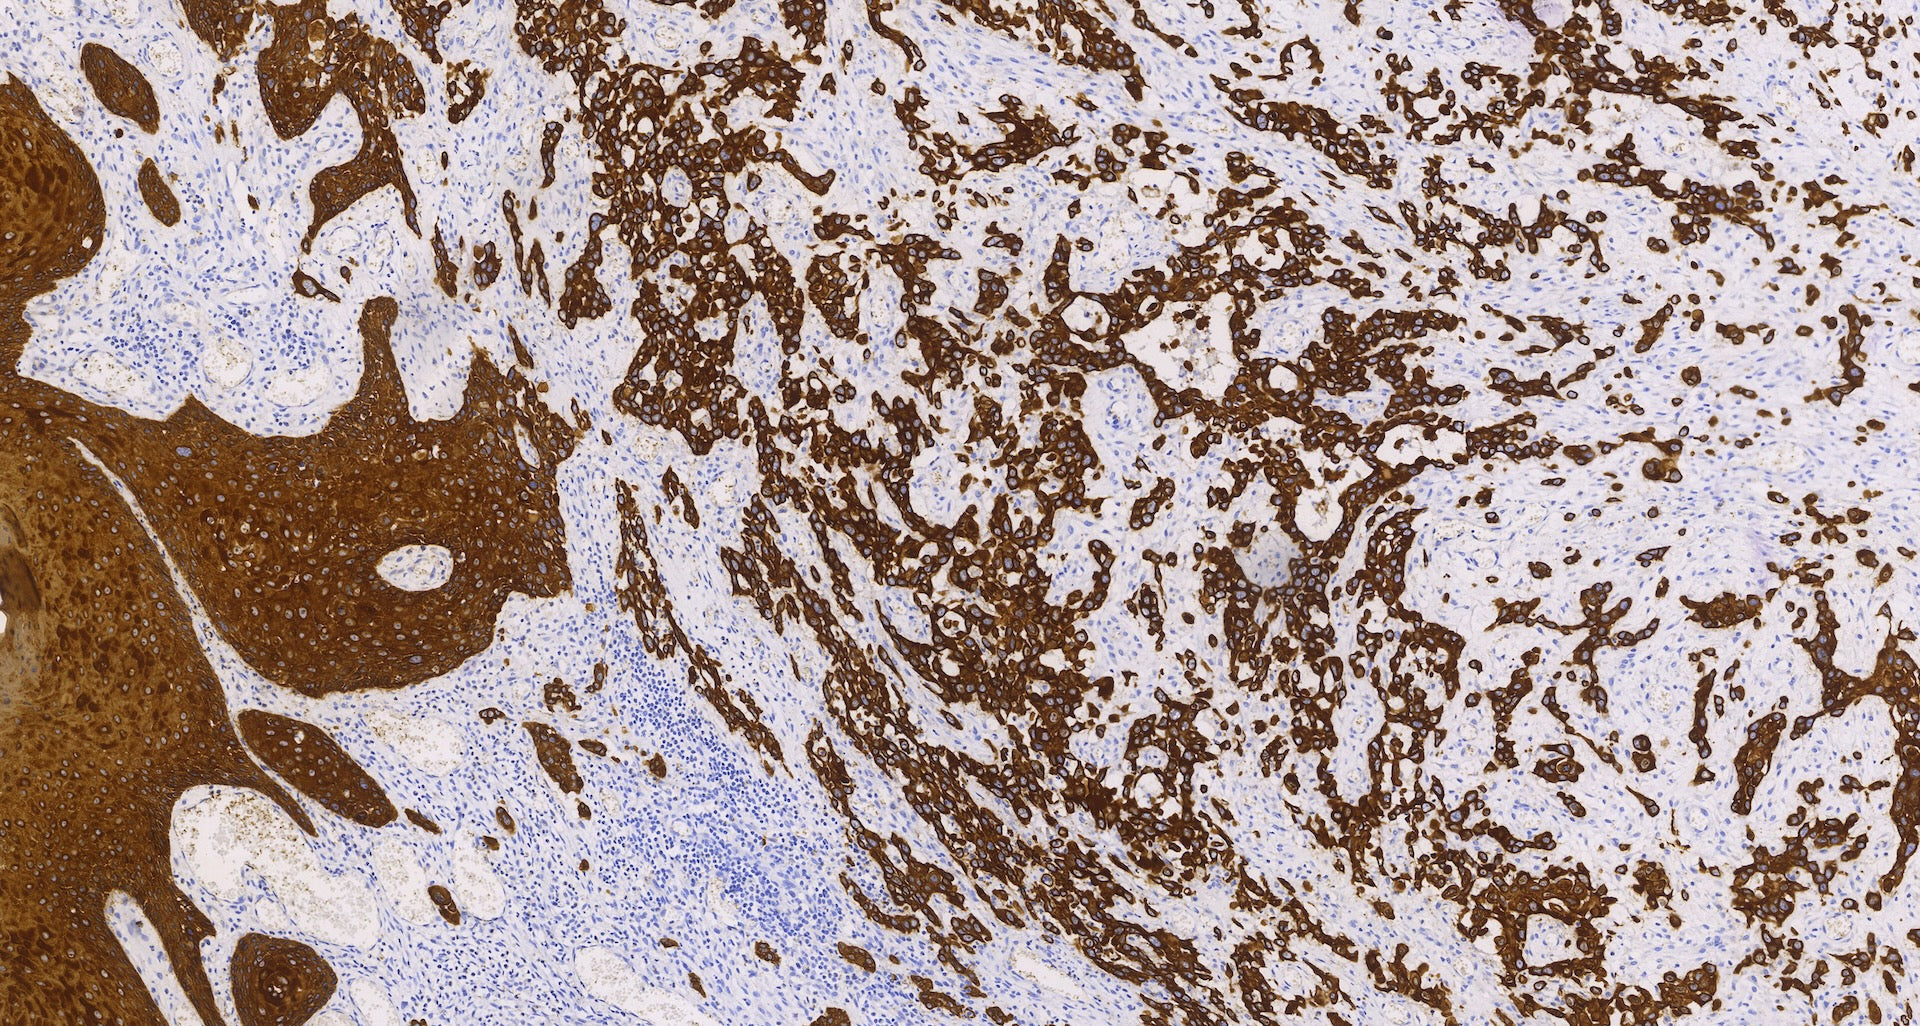

Citoqueratina 5 y 6 (C6H1/C1C8), MMab

La citoqueratina 5 (58 kDa) es un tipo básico de citoqueratina de alto peso molecular que se expresa en varias capas de epitelios estratificados, incluidas las capas de células basales, intermedias y superficiales. También se encuentra en epitelios de transición, epitelios complejos, células mesoteliales y mesotelioma. Por otro lado, la citoqueratina 6 (56 kDa) es otra citoqueratina de tipo básico de alto peso molecular que a menudo se expresa en el epitelio escamoso proliferante y frecuentemente se coexpresa con la citoqueratina 16.

El anticuerpo Cytokeratin 5 & 6 se puede utilizar para detectar la presencia de estas proteínas. Es altamente positivo en casi el 100% de los mesoteliomas malignos, un tipo de cáncer que se origina en las células mesoteliales que recubren la pleura, el peritoneo o el pericardio. Sin embargo, rara vez se observa en adenocarcinomas de pulmón. El anticuerpo también puede ser positivo en carcinomas de células grandes indiferenciados y carcinomas escamosos. Por el contrario, menos del 10% de los carcinomas de mama, colon y próstata muestran positividad para este marcador.

Además, el anticuerpo citoqueratina 5 y 6 se ha empleado con éxito como marcador de células mioepiteliales en la próstata para determinar la malignidad. Las células mioepiteliales son células especializadas que rodean a las células epiteliales en varios tejidos, incluida la glándula prostática.